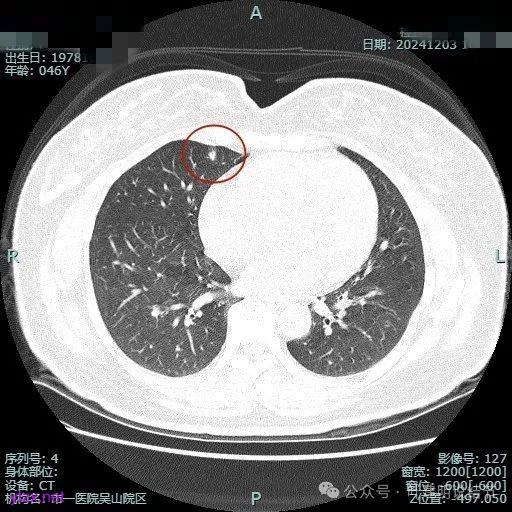

我们先来看2024年9月时的影像:

病灶1:

右下背段混合密度病灶,边上不太清爽,有片状淡磨玻璃影,实性部分密度较高。

感觉病灶有点晕征似的,表面不平,灶内不太致密。

有小血管进入,似有晕征。

离胸膜近但牵拉不明显,病灶边缘有细毛刺,较短且不太锐利。

边缘少许磨玻璃成分,血管进入明显。

瘤肺边界稍显不清。